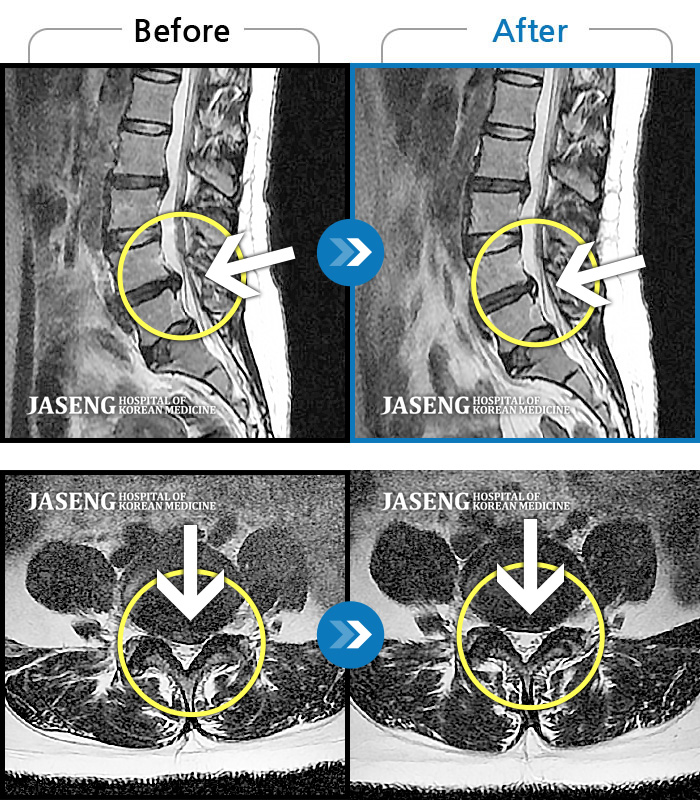

Before

After

환자에게 사전 동의를 받아 동일 조건에서 촬영되었습니다.

개인에 따라 치료 후 부작용이 발생할 수 있으니 의료진과 상담 후 치료를 진행하시기 바랍니다.

좌측 하요추부 통증과 좌측 대퇴 외측면 저림

처음 내원 시 허리 및 좌측 골반부, 하지부 통증 및 저림이 심해서 거동이 힘든 상태였습니다.